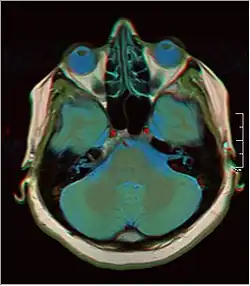

![]() Cross-sectional T1-weighted MRI of a healthy human brain acquired with an ultra high-field MR of 7 Tesla field strength | |